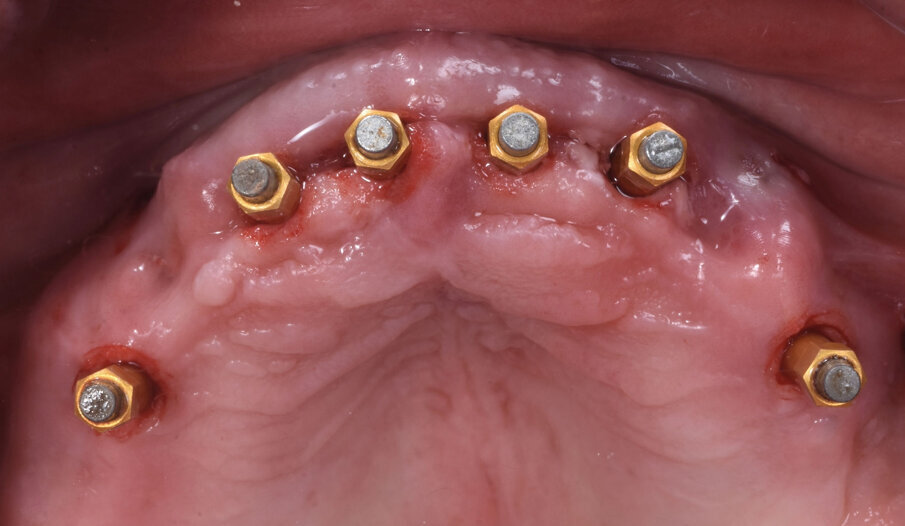

Conseguentemente allo studio effettuato con R2Gate l’azienda produce una guida chirurgica, in questo caso ancorata all’osso residuo, che consente l’atraumatica inserzione degli impianti (Fig. 5). Le fixtures, in questo caso impianti AnyRidge Megagen venivano inserite nelle posizioni designate dallo studio R2G in maniera completamente atraumatica (Fig. 6). La misurazione dell’ISQ (Implant Stability Quotient) confermava con letture superiori a 70 la possibilità di procedere con il carico immediato degli impianti stessi (Fig. 7). Il laboratorio aveva già preparato la struttura con le caratteristiche desiderate dal paziente e dopo l’inserzione dei MUA (Multi Unit Abutments) procedeva alla costruzione della protesi definitiva (Fig. 8).